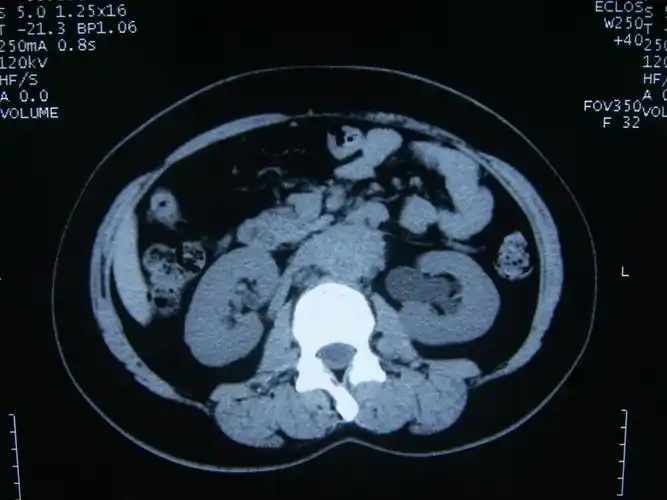

看图讨论一例肾积水病人